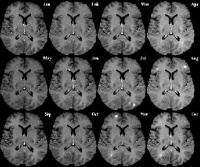

脑部及脊髓核磁共振:最好有显影剂显示新的病灶。在脊髓炎病患、完成脊髓核磁共振後、是否需加做脑部核磁共振的意见仍然莫衷一是。不过、若是定位在脑部的发作、即使是第一次发作、50-65%病患部核磁共振已经有不正常。通常T2-weighted影像是基本的检查、施打显影剂後显示新的T1-weighted病灶表示有急性发作。

目前,国内外对多发性硬化症已有了成熟的诊断标准,主要有3种检查手段可以帮助医生作出正确诊断。第一,脑和脊髓的核磁共振检测;第二,脑积液检查,这主要是检查免疫指标;第三,对视觉、听觉等进行诱发电位检查。